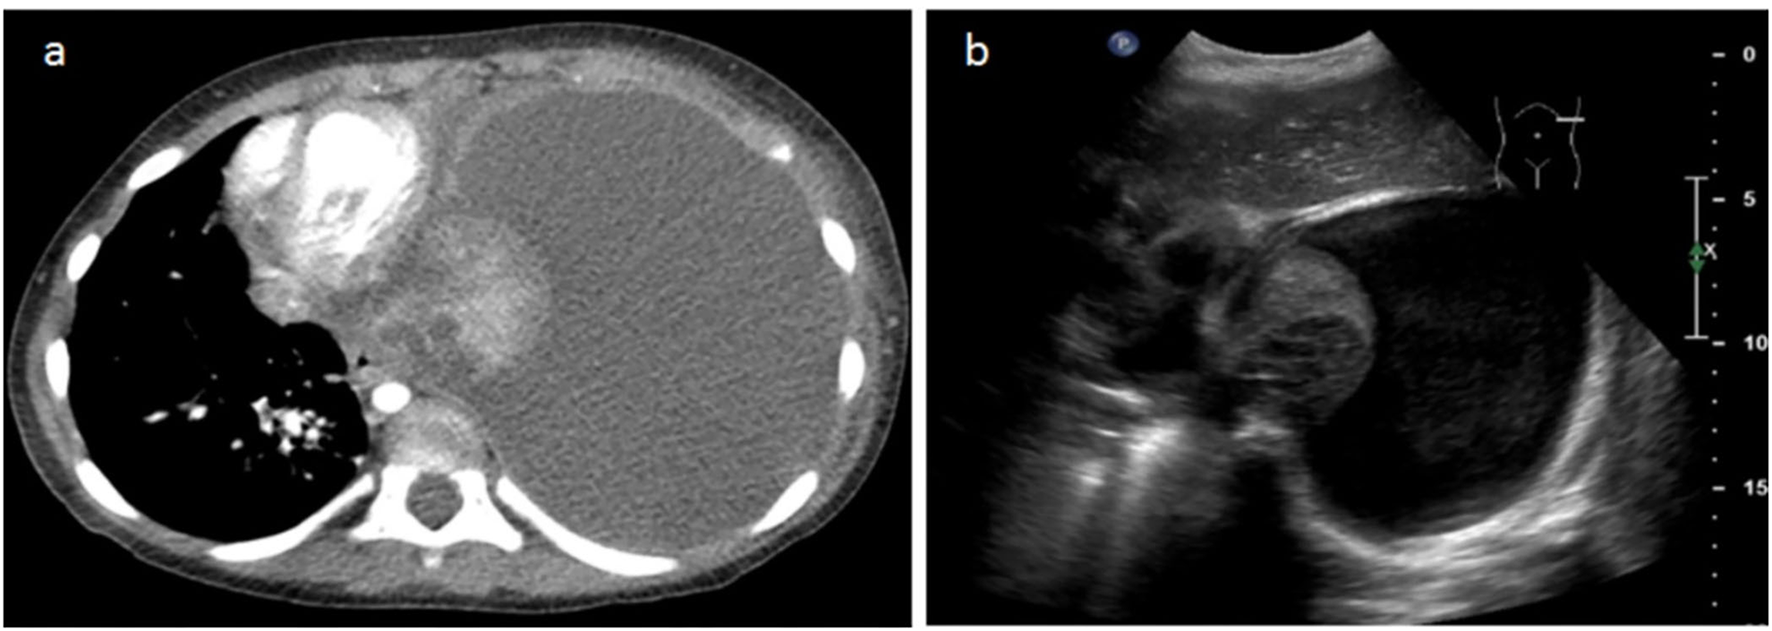

Figure 4

A 3-year-old female patient with severe dyspnea. (a) The transverse slice chest CT demonstrates massive left effusion and atelectasis of the entire left pulmonary parenchyma, with heterogeneous enhancement and round necrotic unenhanced lesions posteriorly. (b) LUS performed the same day demonstrates the same parenchymatous damage with coalescent cystic lesions corresponding to necrosis.